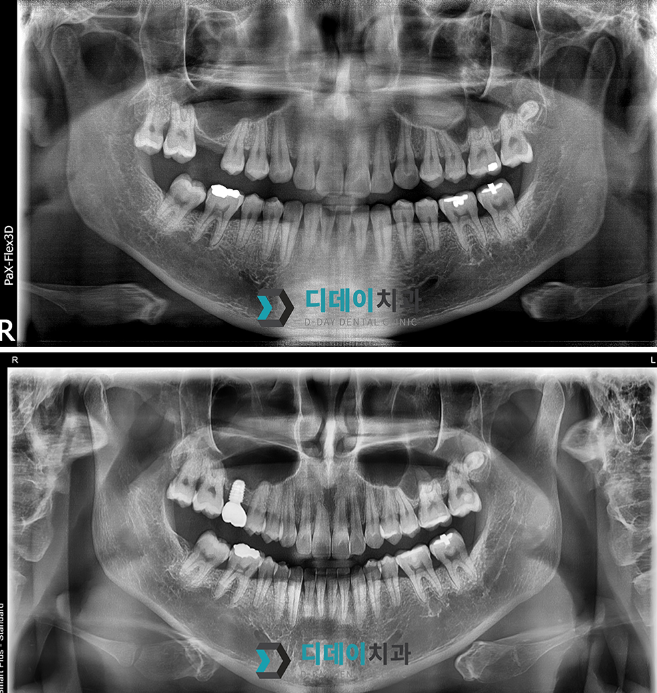

임플란트 (상악동 거상술)

어금니 임플란트 치료를 위해 내원하신 환자분입니다.

2024.07.08